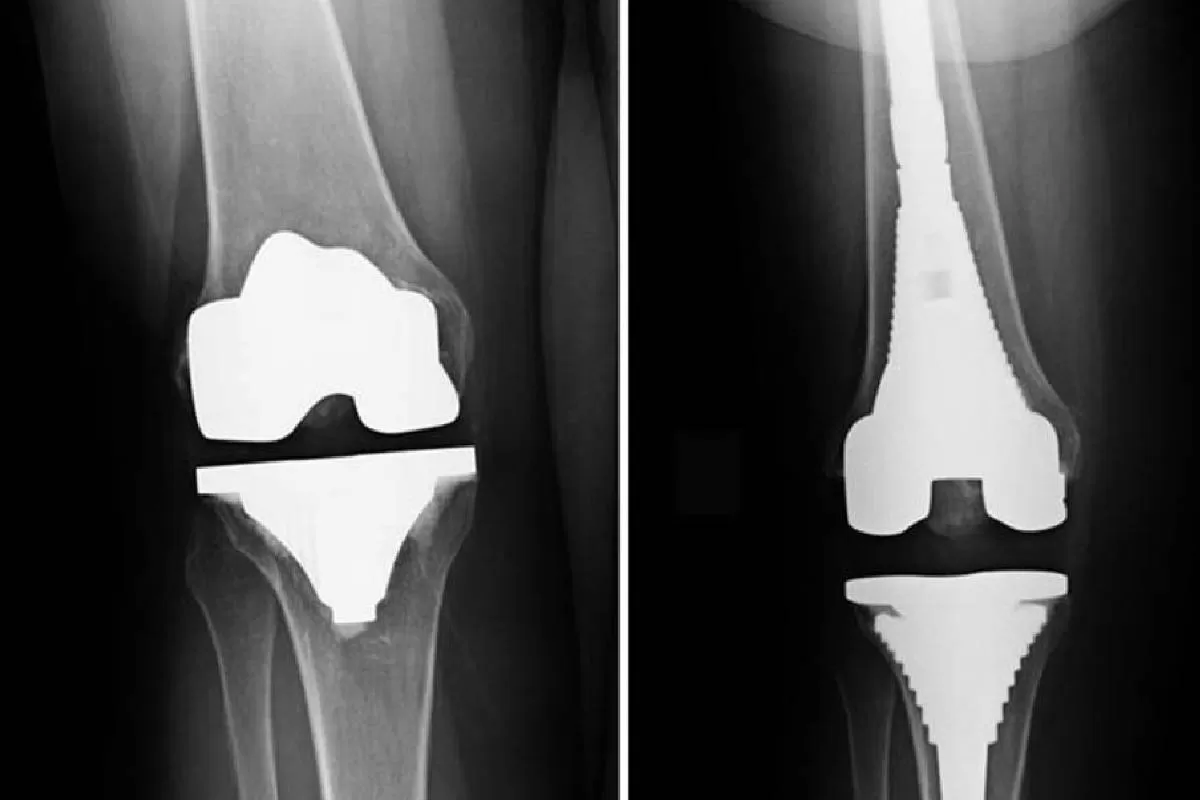

Joint Replacement & Complex Surgeries

For patients with advanced joint damage or severe arthritis, we offer joint replacement surgeries including knee, hip, and shoulder replacements. These surgeries are performed using modern implants and refined surgical planning to ensure long-lasting and natural movement. Complex orthopedic surgeries such as ligament reconstruction, meniscus repair, and deformity correction are also managed with expert precision. Our specialists adopt evidence-based approaches, ensuring each surgical procedure is safe, effective, and recovery-focused.